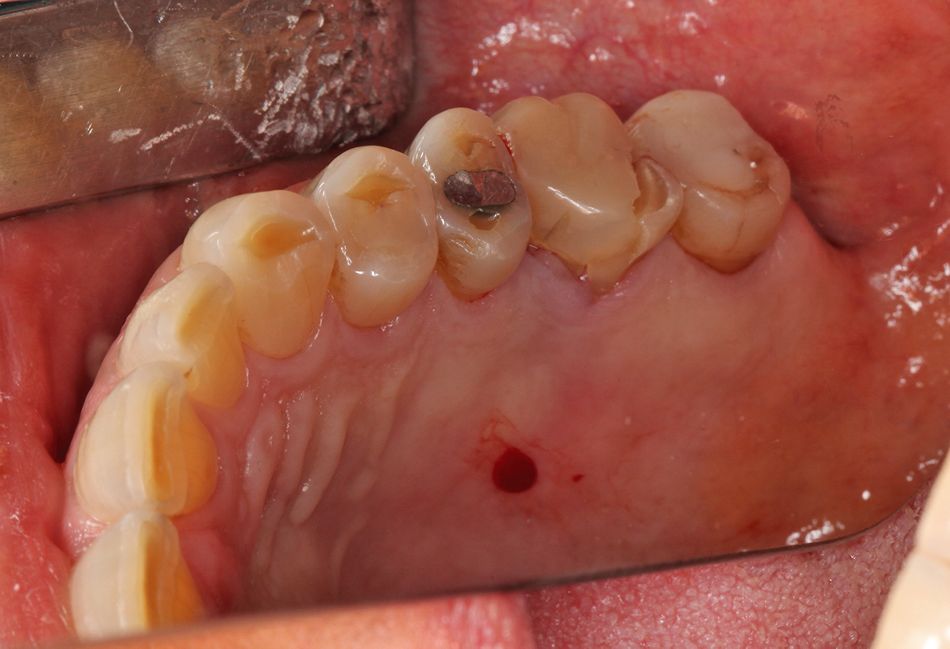

Eine Patientin (59 Jahre) mit nicht erhaltungswürdigen Zähnen 16/17 stellte sich in der Klinik für Mund-, Kiefer- und Gesichtschirurgie der Universitätsklinik Mainz vor (Abb. 2-3). Zusätzlich lag bei ihr eine Rheumatoide Arthritis und eine subtotale Strumektomie (2012) vor, weshalb die Patientin unter der Dauermedikation von Metho­trexat sowie Decortin und L-Thyroxin stand.